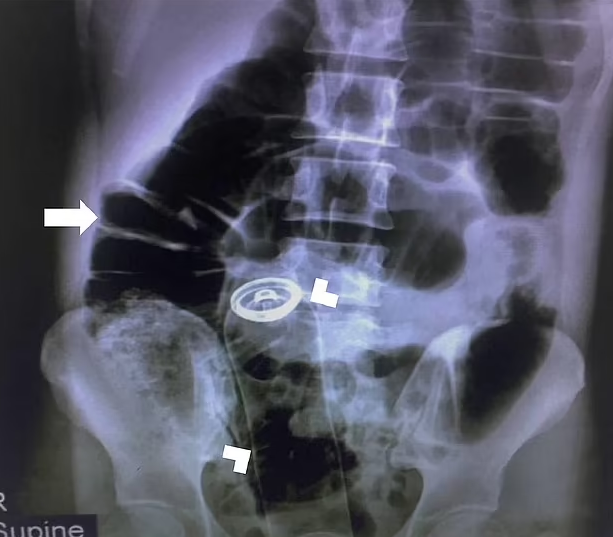

But medics also couldn’t find ‘any part of the canister’, the team wrote in the Visual Journal of Emergency Medicine.

The man was in too much agony to undergo a rectal examination, forcing medics to rely on an X-ray to find where the can had gone.